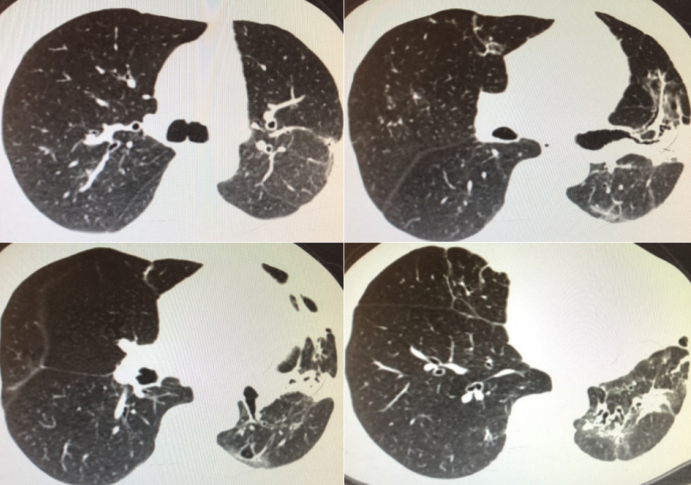

胸部CT(2月20日)(图2)。

前后两次胸部CT对比(2019年2月11日与2月20日),治疗后的胸部CT显示在原有部位上实变进一步加重,结合该患者全身炎症反应综合征存在,是否可应用小剂量全身激素?